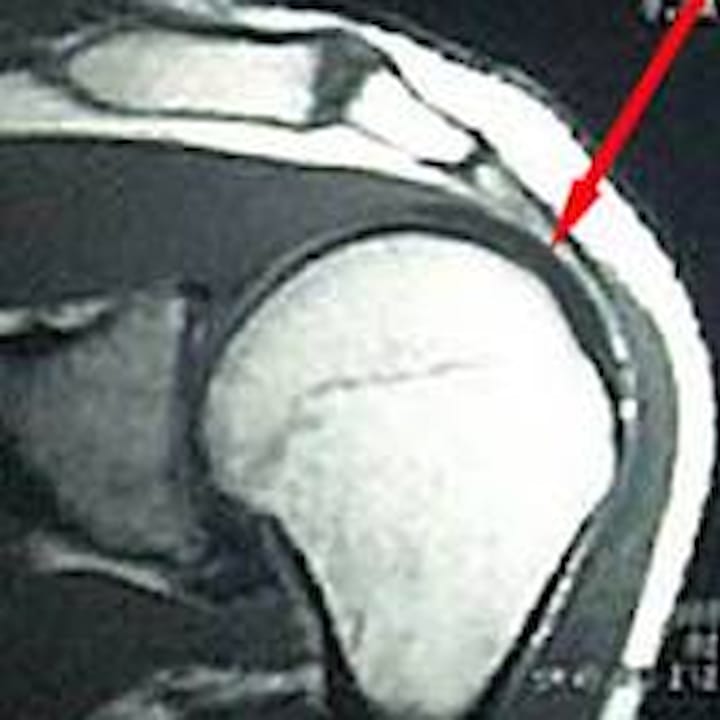

Ein Rotatorenmanschettenriss Rotatorenmanschettenruptur ist ein Riss der eine Sehne der sogenannten Rotatorenmanschette betrifft. Für eine Diagnose ist eventuell eine MRT notwendig. Auch ein Sturz auf die Schulter oder ein plötzlicher Zug bzw.

Das Schultergelenk ist eine komplexe Struktur mit einem Hauptgelenk und drei kleineren Nebengelenken. Ein Labrum-Einriss ist ein Riss des Knorpelrings in der Schulter der die Pfanne umgibt und diese vertieft. Die Rotatorenmanschettenruptur ist eine Schulterverletzung.

Riss der Rotatorenmanschette Die Rotatorenmanschette ist eine Muskel-Sehnen-Platte die den Oberarmkopf umgibt und als wichtiger Bestandteil des Bewegungsapparates der Schulter fungiert. Verletzungen dieses Ansatzes werden. Das Aufwärmen dient der Dehnung der Muskulatur.